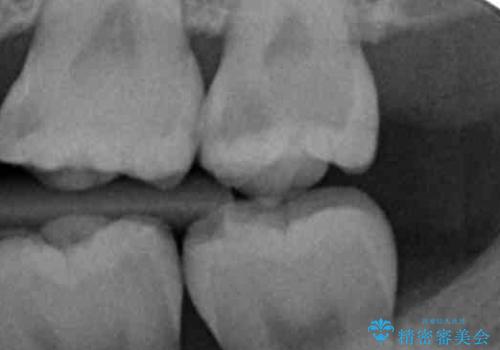

- 奥歯に穴が開いた気がするとのことで来院。

検査の結果、左上の奥歯に大きな虫歯があることが確認できました。

患者様のご希望もあり、今回はセラミックでの治療となりました。

歯の表面に穴が開くほどの虫歯は歯の中でかなり大きくなっていることが多いです。

虫歯の除去後は適合の良い修復物を入れることで今後の虫歯リスクを減らします。